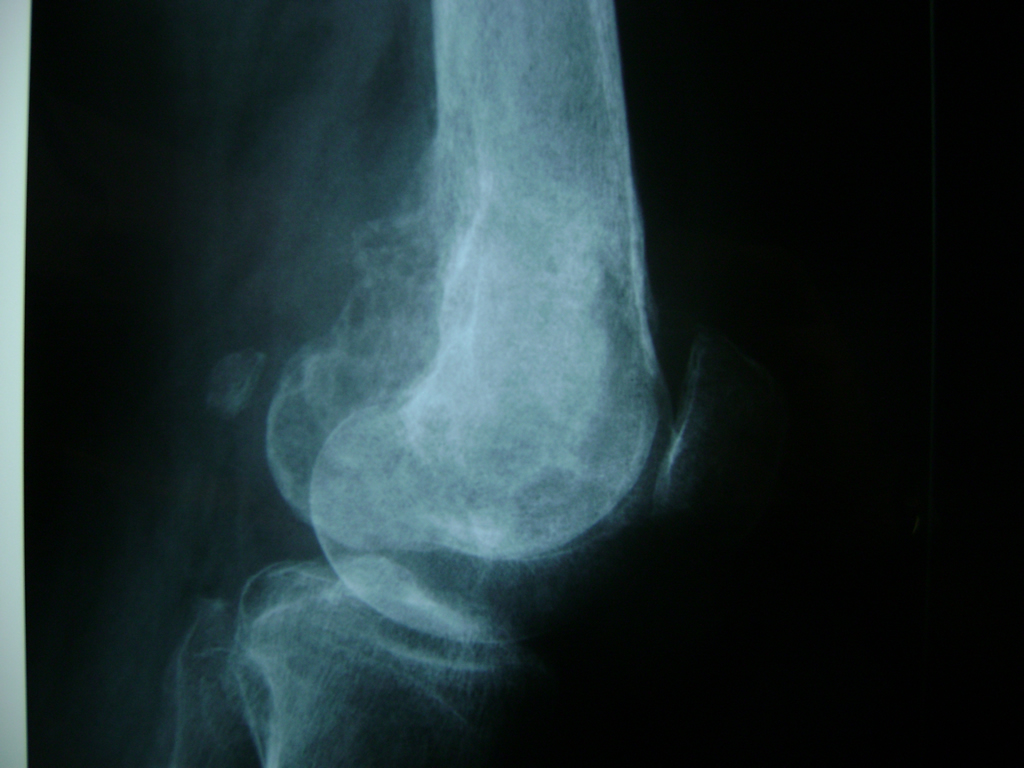

Cirugías de Codo - Rodilla

La artroscopia de rodilla es un cirugía en el cual la estructura interna de la articulación es examinada ya sea para realizar un diagnostico o para realizar un tratamiento, este procedimiento se realiza utilizando un instrumento parecido a un pequeño tubo llamado artroscopio.